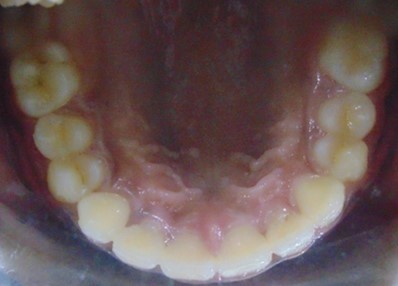

Before

After

Image 1